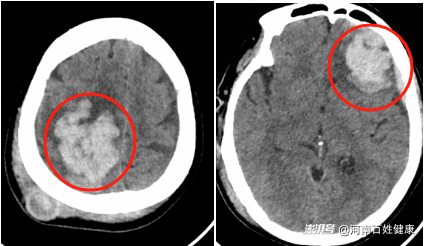

復(fù)查CT提示:右側(cè)額頂葉腦出血較前范圍增大;左側(cè)額葉腦出血較前新增;左側(cè)額部硬膜下血腫較前明顯增多,此時劉奶奶已出現(xiàn)嗜睡癥狀,情況危急需立即手術(shù)治療。

全麻成功后,在副主任醫(yī)師段友強及團隊的配合下,右側(cè)頂枕部頭皮被切開約5cm骨窗,借助顯微鏡醫(yī)生小心翼翼地剝離了血腫,每一步都精準(zhǔn)避開腦血管——這里的血管細如發(fā)絲,稍有不慎就會引發(fā)二次出血。

第二步:轉(zhuǎn)戰(zhàn)左側(cè)額葉

清除右側(cè)血腫后,手術(shù)團隊迅速調(diào)整體位,在左側(cè)額部開顱。醫(yī)生用吸引器輕柔抽吸,配合生理鹽水反復(fù)沖洗,最終清除約30ml血凝塊。